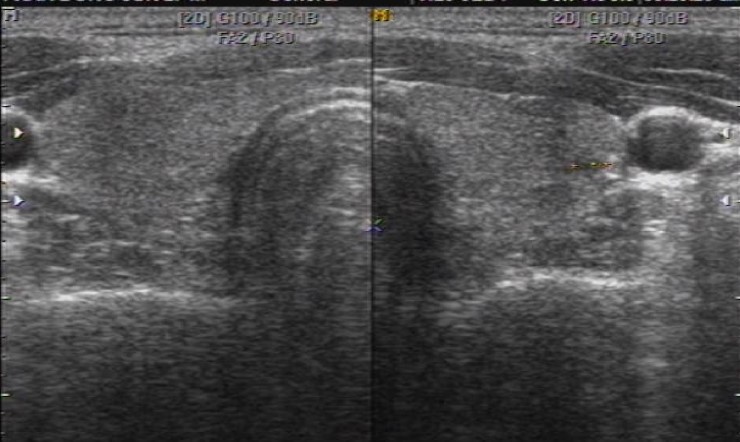

왼쪽 경동맥에 접해서

T nodule L 12.7*5.4*10.3(hypoechoic, lobulated margin, microcalcification at upper lesion)

초음파상 위험소견이 3개 관찰되어 세침검사를 요함.

7년전 초음파 사진을 참조하면 경동맥 옆에 같은 위치에 2.9 mm 작은 결절 소견